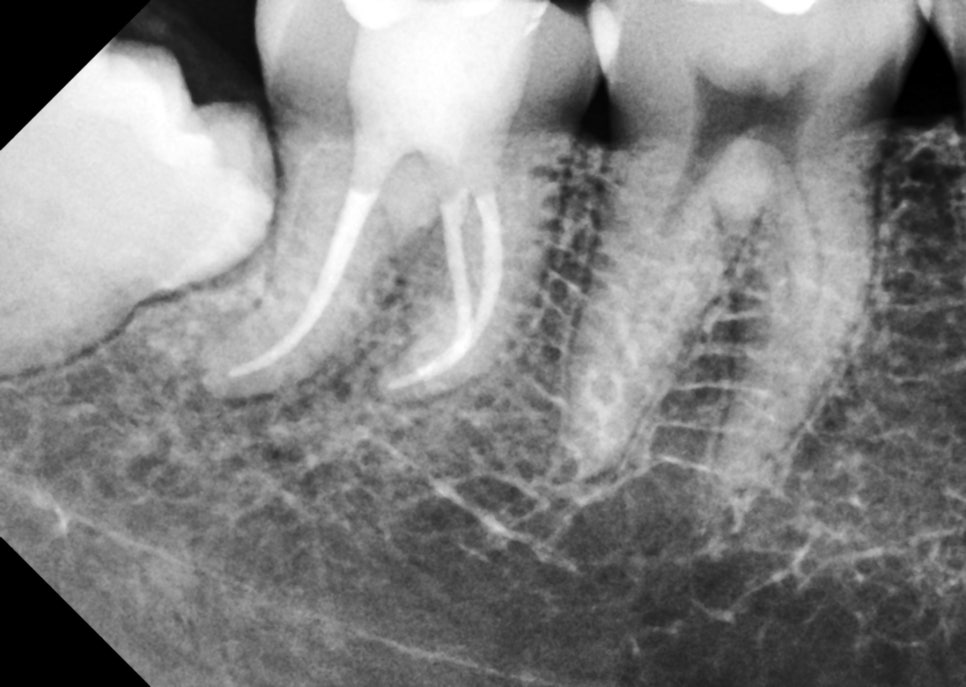

촬영일 : 250617

이처럼 까다로운 구조였음에도

서초동치과에서는 반복적으로

CT와 방사선 진단을 통해

근관의 해부학적 구조를 정밀하게 파악하고

전 과정에서 철저한 감염관리와

방습 상태를 유지한 채

신경치료를 성공적으로 마무리할 수 있었습니다.